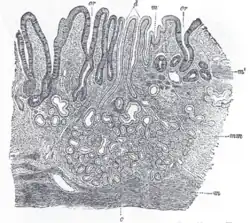

The small intestine, where most of the absorption occurs, is divided into three sections, the duodenum, the jejunum, and the ileum. In all three sections the layers follow the general pattern:

The surface for absorption is increased in many ways: the mucosa of the small intestine is thrown into folds called rugae; the mucosa itself has numerous finger-like projections called villi, and the epithelial cells are also covered with numerous projections called microvilli. The microvilli give the appearance of a 'brush' on light microscopy; hence the term brush border. The following illustration shows the anatomy of a villi:

Mucous is secreted by numerous goblet cells; other cells are specialized for absorption and are known as absorptive cells. In the base of the crypts are numerous secretory cells which secrete the digestive enzymes of the small intestine. Some of the crypts penetrate into the submucosal layer, forming digestive glands which will communicate with the mucosa via a secretory duct.